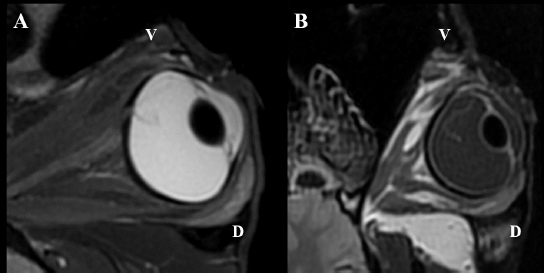

Fig. 5. MRI OS, case 2. T2W oblique plane image highlighting the hypointense-detached retina reaching the optic disk and in direct continuity with the optic nerve. Note the hyperintense periphery of the optic nerve, corresponding to the normal thin layer of cerebrospinal fluid surrounding it (A). FLAIR frontal plane image showing the difference of signal between the slightly hyperintense retina within the hypointense vitreous chamber (B). D: dorsal; V: ventral.

Intraocular lesions found on US and MRI of both horses were consistent with the ophthalmic examination. Complete RD OS and hyperechoic vitreous floaters OU were noted on US (Fig. 4). RD was also evident OS on MRI, more conspicuously on T2W and FLAIR sequences. In T2 sequences, the detached retina was identified as a V-shaped membrane of intermediate signal inside the hyperintense vitreous and reaching the optic disk (Fig. 5A), while it was slightly hyperintense in comparison to the hypointense vitreous chamber on FLAIR acquisitions (Fig. 5B). There was a subjectively abnormal positioned optic disk OU on US and MRI, suggesting ectopic ONH. OS was flattened at the level of the ONH in both horses. Except for a subarachnoid emphysema due to postmortem changes, the brain looked otherwise normal on MRI. Based on US, the axial globe length measured 39.2 mm OS and 41.5 mm OD of case 1 and 45 mm OU in case 2.